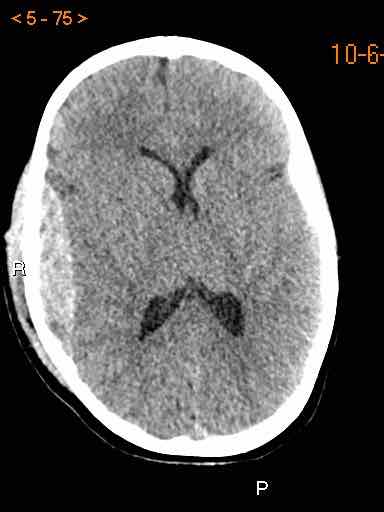

Tụ máu dưới màng cứng đồng tỷ trọng

Khi tụ máu dưới màng cứng tiến triển theo thời gian, tỷ trọng của khối tụ máu sẽ giảm dần và có thể tương đương với tỷ trọng của nhu mô não, khiến việc phát hiện tổn thương trở nên khó khăn.

Đây là trường hợp tụ máu dưới màng cứng đồng tỷ trọng rất khó phát hiện (các mũi tên).

Lưu ý rằng ở mức cắt cao hơn có tụ máu dưới màng cứng hai bên.